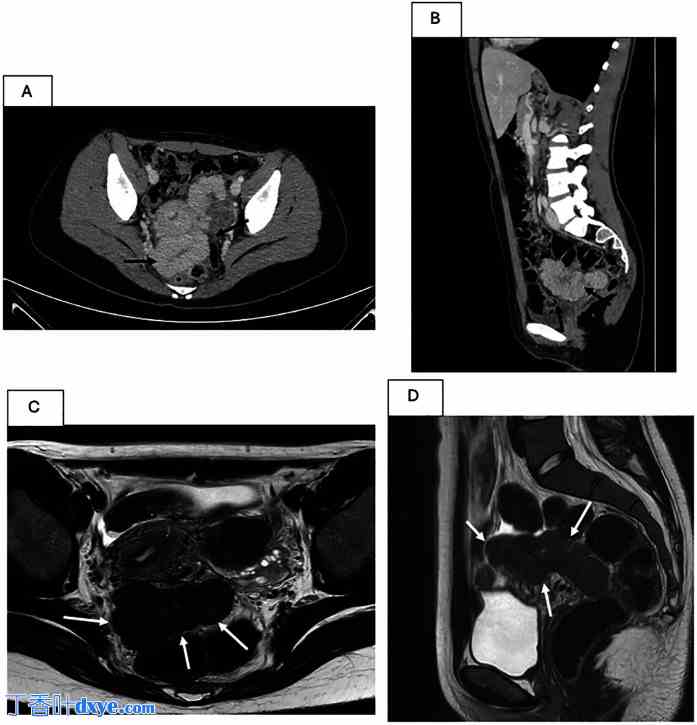

图 2.

盆腔脾脏的 CT 和 MRI 影像。(A,B) CT 扫描。黑色箭头在轴向 (A) 和矢状面 (B) 中指示一个尺寸为 120 × 60 × 55 mm 的匐行结构,在门静脉期具有均匀的增强。(C,D) MRI。白色箭头指示多分叶肿块,边缘规则,包含融合性假结节,形态细长(轴向尺寸为 10 × 4.7 cm,头尾方向延伸约 6.3 cm),在轴向 T2 加权像 (C) 和矢状位 T2 加权像 (D) 中位于子宫和直肠之间。